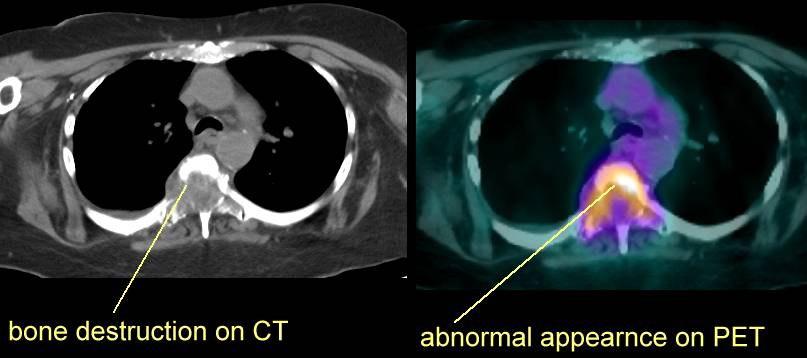

PET Scans of Bone Metastases

PET scans may show these lesions best (go here , here, here, here, here, here, here , here , here , here , here , here , here and here) even better than CT scans (go here , here, here and here) and better than MRI (here). PET scans also show the response to radiation (go here). PET is helpful for hard to see areas like the ribs or scapula. PET's may be best for

osteolytic lesions and bone scans best for blastic metastases (go

here). |